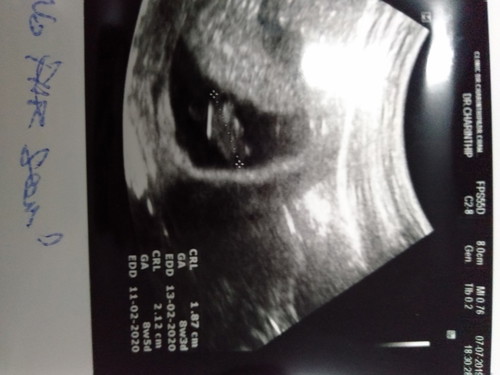

อายุครรภ์ 9 สัปดาห์ 5วัน แต่ usดู น้องได้แค่8สัปดาห์ 5วัน คุณหมอบอกว่าแม่เป็นพาหะ เม็ดเลือดเเดงเล็กผิดปกติ โอกาสแท้ง 50/50 คุณหมอนัดฟังผลเลือดสามี วันที่16นี้ มีใครมีประสบการณ์แบบนี้ไหมคะ เล่าให้ฟังหน่อยค่ะ

อายุครรภ์ยึด US เป็นส่วนใหญ่ค่ะ แต่เวลาคลอดเค้าก็จะเทียบกันอยู่แล้ว